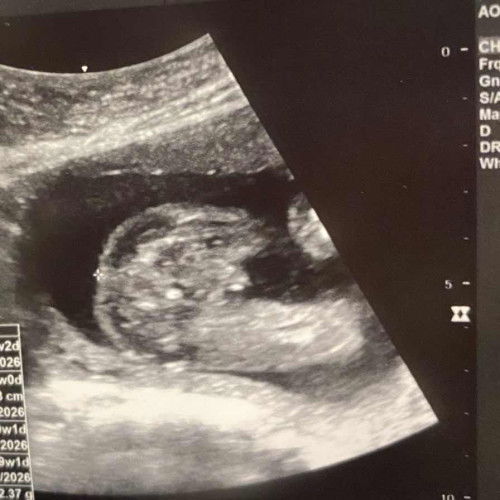

38 minggu 1 hari ngam Harini!!

Nak tanye mummy2 smue kalau perut senak sakit mencucuk kiri kanan pinggang adakah tanda2 nak bersalin sebab ni anak kedua masa anak first tak rasa apa tau tau doktor scan cakap air ketuban dah tkde terus ke hta tanpa rasa sakit tapi mengandung yang kedua kali ni rasa tak cukup nafas dan akhir2 ni perut rasa tegang je semlm chekup kk cakap baby dah masuk laluan,saya tkde turun tanda apa apa hanya sakit mengeras dan rasa dibahagian pinggang belakang mencucuk mintak pendapat dekat mummy2 yang tau tentang ni saya nak pergi hta pun risau nanti takot diorang suruh balik semula rehat dekat rumah pula . #mohonbantujawabbunda